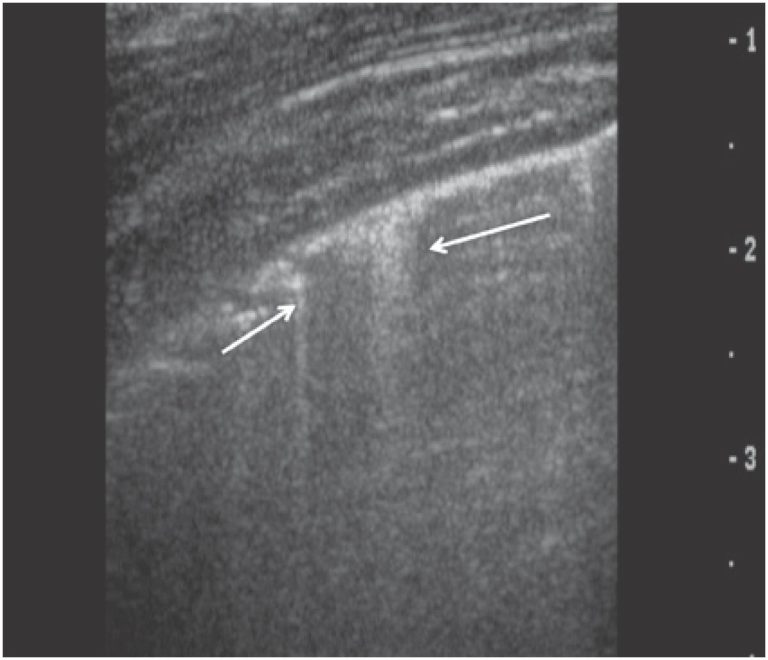

O exame ultrassonográfico do tórax avançou nas últimas décadas, sendo utilizado para o diagnóstico de inúmeras condições patológicas, e fornecendo informações qualitativas e quantitativas. Os pulmões aerados e o arcabouço ósseo do tórax representam barreira sonora para o estudo ultrassonográfico, gerando artefatos que, bem conhecidos, são utilizados como ferramentas diagnósticas. Eco pleural normal, linhas A, linhas B, linhas C, linhas E e Z (conhecidas como falsas linhas B) são artefatos com características peculiares. Os padrões de consolidação e de pneumotórax também são bem estabelecidos. Alguns protocolos têm sido utilizados no manuseio dos pacientes: Blue Protocol, Protocolo FALLS e Protocolo C.A.U.S.E são exemplos de três propostas que, por meio da associação entre os artefatos, permitem sugerir diagnósticos precisos. A ultrassonografia de tórax, aliada à radiografia de tórax, muitas vezes é suficiente para o diagnóstico e a conduta das afecções pulmonares e da parede torácica. Trata-se de ferramenta diagnóstica de grande valia para médicos radiologistas, emergencistas e intensivistas.